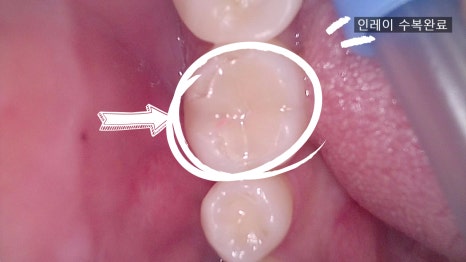

④ 장착

– 7일 후 내원하여 완성된 인레이를 장착하고 교합을 체크한 뒤 마무리합니다.